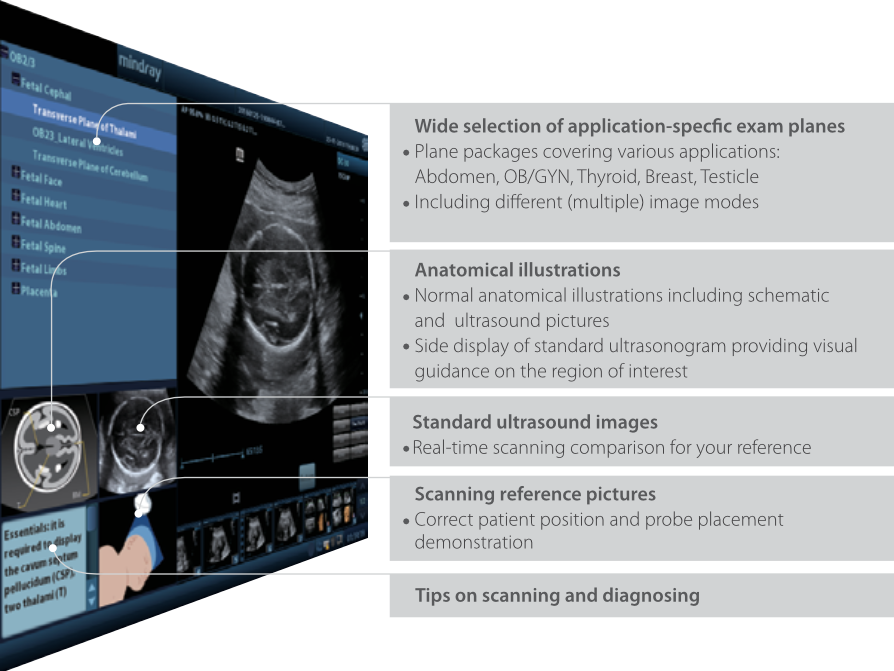

iScanHelper

????? ??? ??? 'how & what'? ?? ???? ???? ?? ??? ?? ?????. iScanHelper?? ???? ??, ?? ??? ??, ?? ?? ?? ? ??? ??? ?? ?? ???? ????.